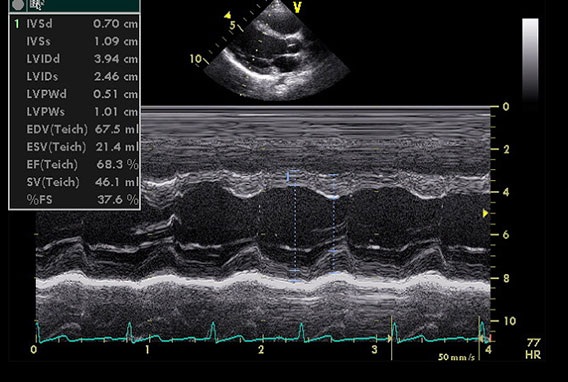

LV测量值的超声心动图像(胸骨旁长轴观)

心脏结构变化和异常ECG可能对医生区分是运动员的心脏(“运动员的心脏”)改变,还是病理性心肌病(例如,HCM,扩张型[DCM],致心律失常性右心室[ARVC])构成挑战。虽然左房扩大常见于运动员的心脏和HCM,其他特征有助于鉴别这些情况,分别包括以下内容:

• LV舒张期内径绝对值:≥55mm vs. <55mm

• LV舒张期充盈:正常vs.变异

• HCM家族史:否vs.有

• 极大摄氧量(VO):正常或增加vs.减少

运动员心脏的生理变化或病理变化(如,轻度HCM)均可出现LV壁厚度13~15mm。左心室壁测量值落在这个范围内的患者仍有必要进一步评估。